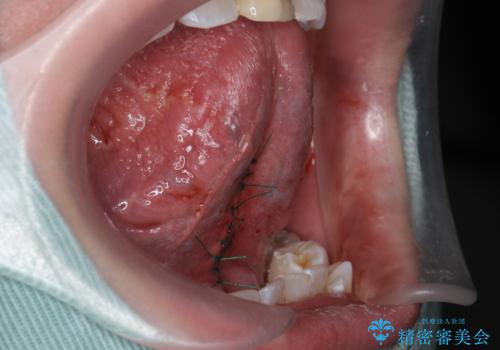

- 滑舌が気になるため舌小帯を切りたいとのことで来院された患者様です。

舌小帯切除を行い、滑舌の改善をはかります。

治癒も良好で、しゃべりやすくなったと大変喜んでいただけました。